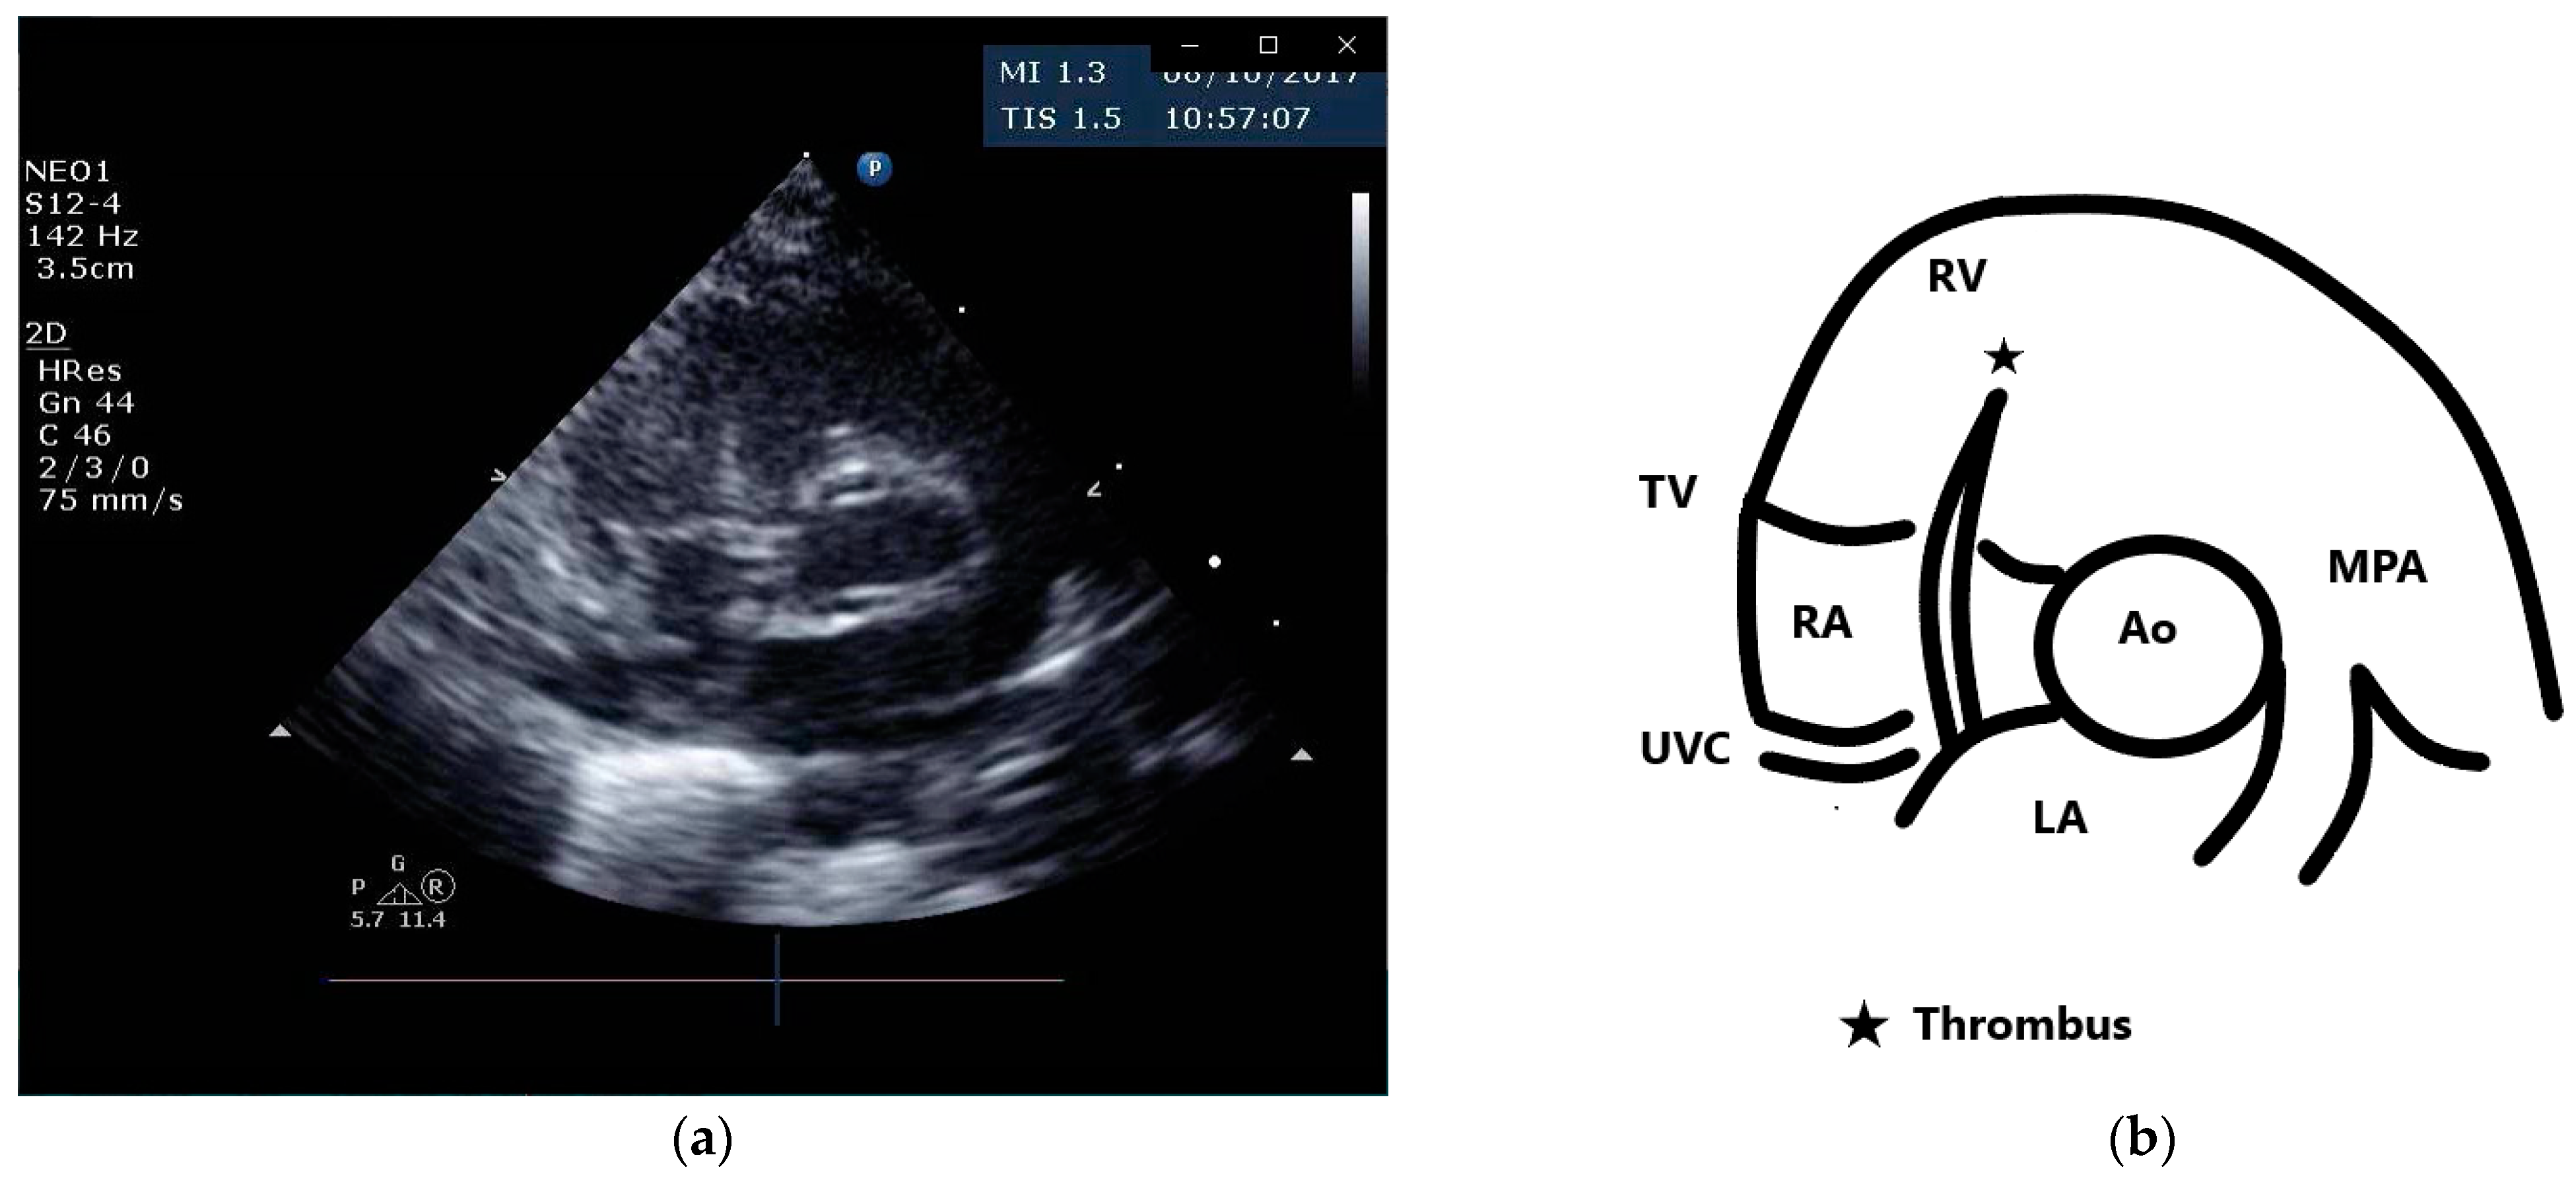

2. Case Presentation

3.5. Echocardiographic Diagnostic Features of Intracardiac Thrombi